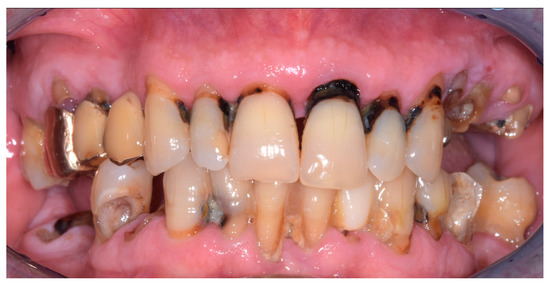

During the intraoral examination, multiple failing teeth were noted in both the maxillary and mandibular arches (Figure 2).

Figure 2. Intraoral frontal view of the patient’s dentition in occlusion.